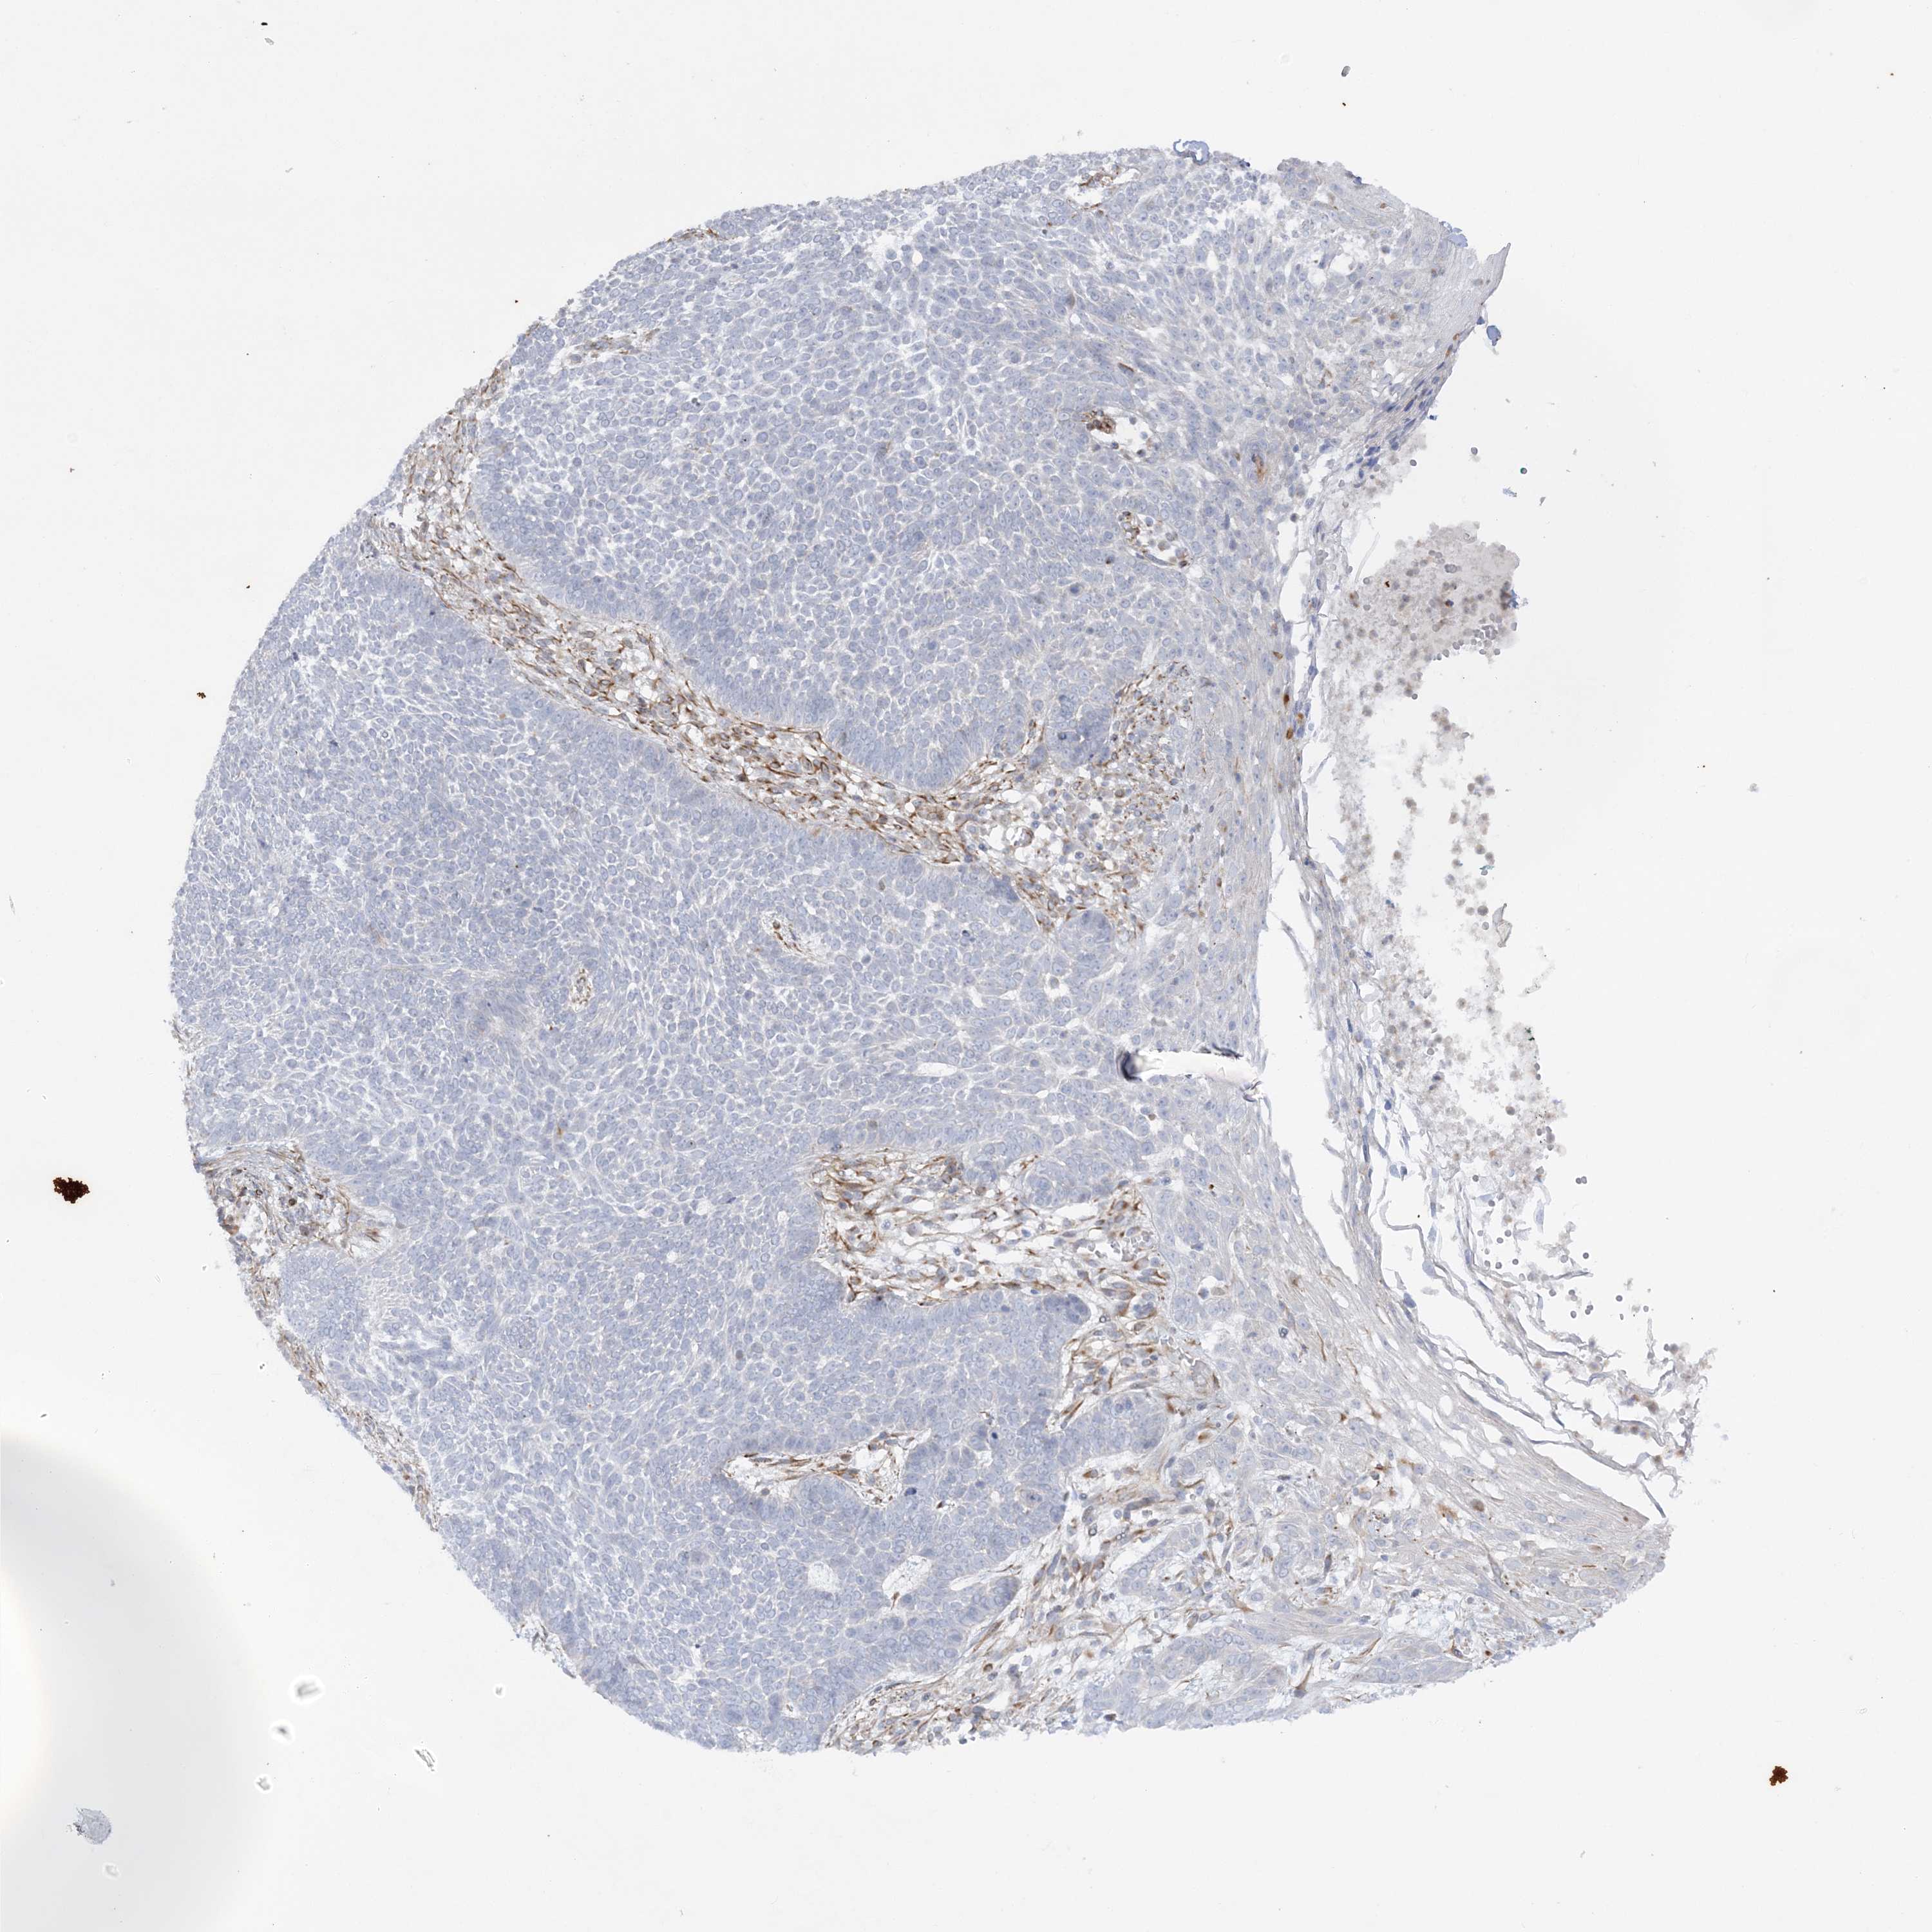

Basal cell and squamous cell cancer

SKIN CANCER - Protein expressioni

A mouse-over function shows sample information and annotation data. Click on an image to view it in a full screen mode. Samples can be filtered based on level of antibody staining by selecting one or several of the following categories: high, medium, low and not detected. The assay and annotation is described here.

Antibody stainingi

Antibody staining in the annotated cell types in the current human tissue is reported as not detected, low, medium, or high, based on conventional immunohistochemistry profiling in selected tissues. This score is based on the combination of the staining intensity and fraction of stained cells.

Each image is clickable and will lead to virtual microscopy that enables deeper exploration of all samples and also displays staining intensity scores, fraction scores and subcellular localization as well as patient and tissue information for each sample.

Antibody HPA036560

Antibody HPA036561

Staining

High

Medium

Low

Not detected

Intensity

Strong

Moderate

Weak

Negative

Quantity

>75%

75%-25%

<25%

None

Location

Nuclear

Cytoplasmic/membranous

Cytoplasmic/membranous,nuclear

Squamous cell carcinoma, NOS

Squamous cell carcinoma, metastatic, NOS